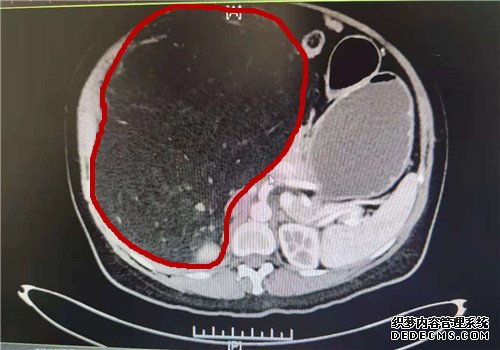

术前CT图,红圈部位为肿瘤

“住院之后,我们对她进行了进一步的检查,做了全腹部的增强CT。”泌尿外科徐光勇教授回忆说,CT结果显示该巨大包块最大截面约有274*192mm,来源于右肾,可能是血管平滑肌脂肪瘤。

在患者右侧腹直肌处切开长约25cm的切口,逐层进入腹腔后,一个巨大的肿瘤呈现在医生们的眼前。“肿瘤在腹腔右边,看起来大约20*30cm。因为太大,把旁边的脏器都挤压到左边去了。”徐光勇教授说。